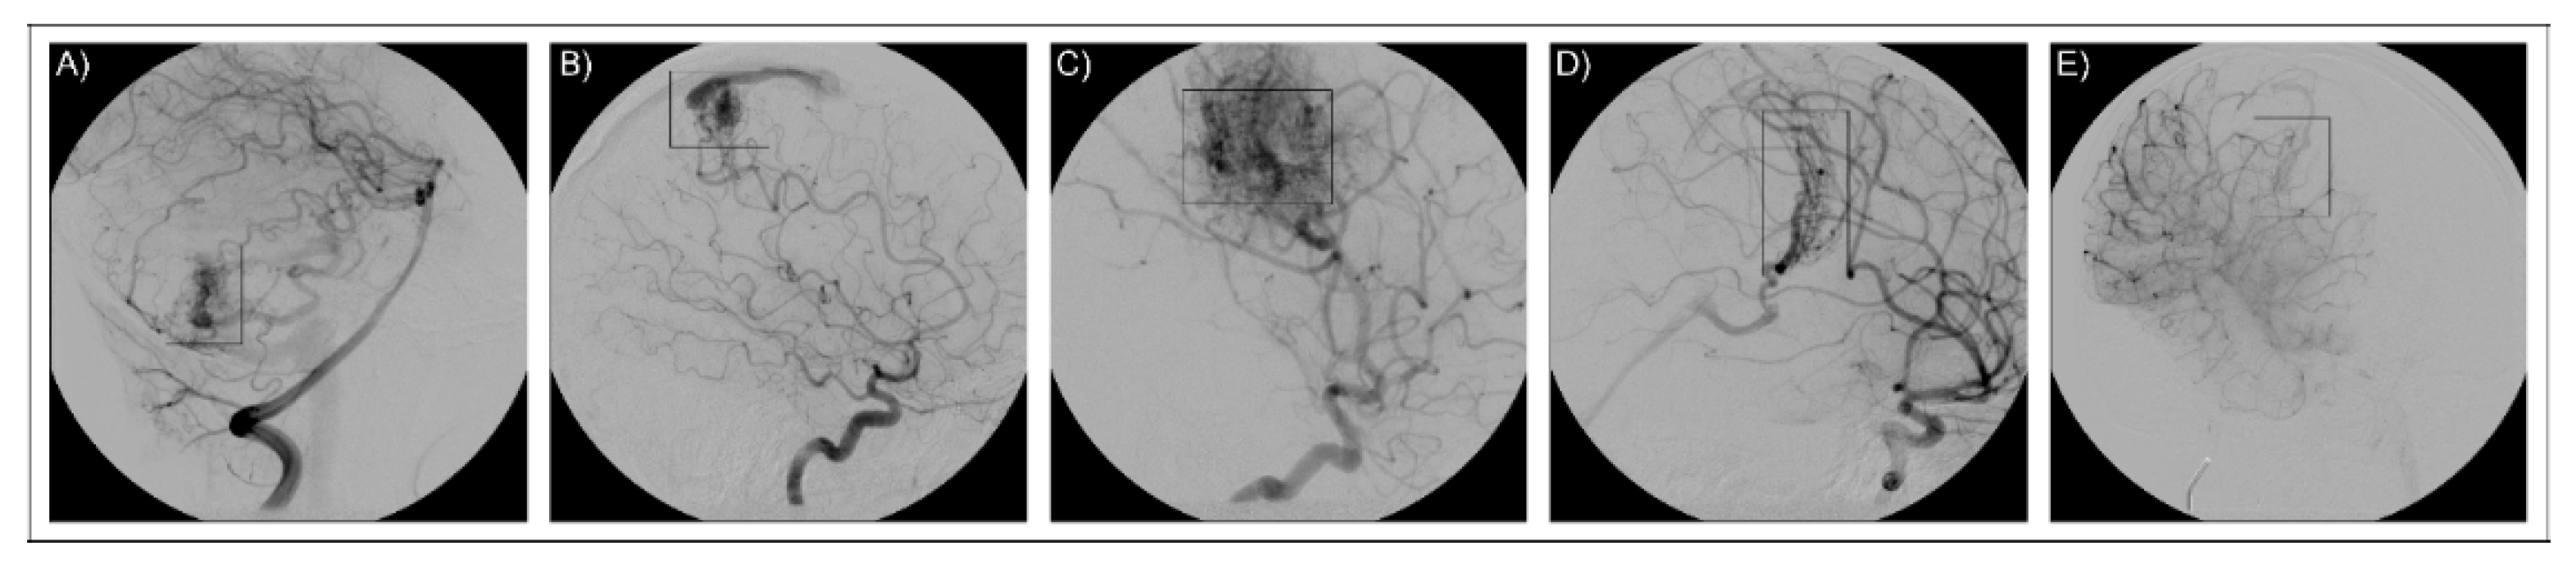

| Patient | Sex | Age (Years) | Age of Onset (Years) | Symptoms | Lesion Number | Spetzler–Martin Grading |

|---|---|---|---|---|---|---|

| AVM1 | M | 14 | 12 | Intracerebral hemorrhage following AVM rupture | 1—parietal left area | 2 |

| AVM2 | M | 31 | 18 | Tremor of the left leg, diffuse tremor, seizures | 1—front-parietal left area (not bleeding) | 2 |

| AVM3 | F | 32 | 29 | Dizziness, tinnitus, seizures nausea right hemiparesis visus reduction | 1— parietal left area | 3 |

| AVM4 | F | 8 | At birth | Drowsy status, finalistic limb movement | 1—proliferative microangiopathy, central left area | 3 |

| AVM5 | M | 7 | 5 | Sudden headache, vertigo, seizures | 1—anterior-parietal paramedian right area | 2 |